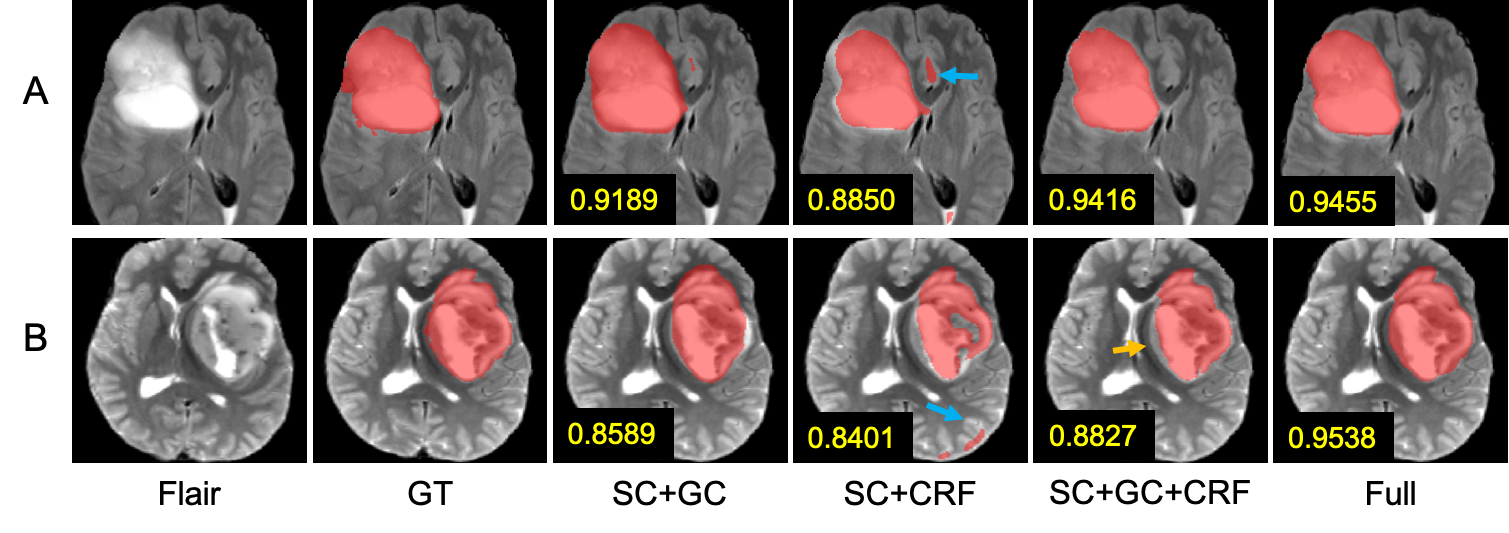

Refer to caption

Figure 3: Results of another four sample slices (C-F) on different settings in Phase 2. Samples in red box are the mislabeled results.

Our task for Phase 2 is very challenging because there is no pixel-level labels, but only the existence of TC and ET in the training. As shown in Table 1 Phase2, there are still some room for improvement compared with the fully supervised model and the weakly supervised model using scribbles of all the substructures extracted from the GT mask. We still see lots of improvements from our hybrid unsupervised and weakly supervised method compared to the report of other unsupervised methods on brain tumor dataset, which only get Dice score around 60% for TC and ET [6]. The WT still keeps a high score due to our hierarchical segmentation process. In Fig. 3, we can see that when assigning high loss weight to the k-means scribbles, the model gives a better performance on TC and ET segmentation in sample C,D, and TC dice score is greatly increased to 70%similar-toabsentpercent70\sim 70\% in Table 1. The reason is that scribbles contain more correct labels when compared with k-means masks which have unreliable labels on the boundaries. Unsuccessful results are also reported in Fig. 3, where ED and NET are mislabeled in F, possibly due to their similar feature and appearance in k-means clustering.